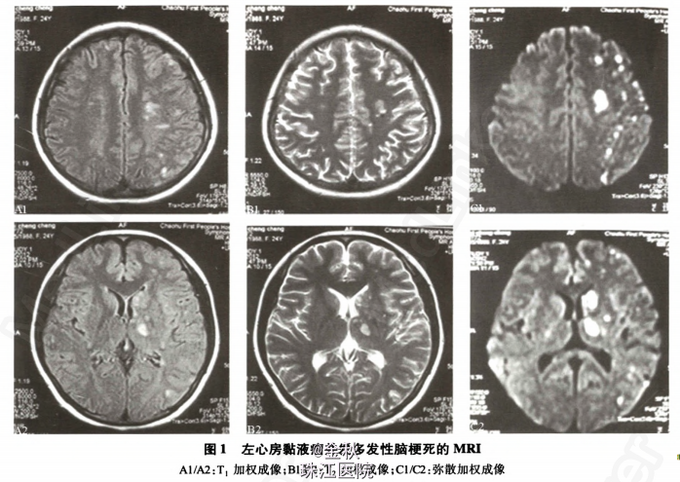

患者,女性,24岁。因“右上肢乏力、麻木4天”入院。患者于4天前活动时觉右上肢乏力伴麻木感,无头晕、头痛,无下肢麻木等,起初未引起注意,但症状一直无缓解,遂于昨日就诊当地医院,查MRI示“左侧大脑半球多发性散在梗死灶(图1)”,考虑“脑梗死”,为进一步治疗转入我院。余病史无特殊。

诊断——左心房粘液瘤并多发性脑梗死。 处理——人院后予阿司匹林抗血小板,低分子肝素钙抗凝以及活血等治疗。确诊后,患者在人院第4天转心胸外科行心脏肿瘤切除术,术中见肿瘤位于左心房,大小约30mmX 40mmX 40mm,有一窄蒂连于房间隔,完整摘除左心房肿瘤。术后病理学检查:心脏黏液瘤(图3),肿瘤大小25mmX20mmX12mm。术后第6天复查超声心动图:二尖瓣轻度返流,少量心包积液(图2B)。